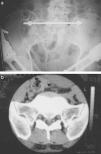

La radiografía de pelvis realizada a la llegada del paciente al centro evidenció una amplia diastasis de la sínfisis púbica, una fractura en la región sagital media del sacro y una fractura de la apófisis transversa derecha de la quinta vértebra lumbar (fig. 1a). Dado que la situación hemodinámica del paciente permanecía estable, se realizó a cabo una tomografía axial computarizada (TAC) de la pelvis para intentar identificar más claramente la lesión (fig. 2a,b). La TAC confirmó la orientación sagital media de la fractura sacra, sin detectarse anomalías concomitantes en las articulaciones sacroilíacas de ambos lados. A causa de la amplia diastasis de la sínfisis púbica, se decidió realizar una estabilización anterior con un fijador externo de pelvis. Se optó por colocar pines en la zona anterior de la cresta ilíaca (fig. 1c). El paciente permaneció estable intraoperatoria y postoperatoriamente, sin que se registraran cambios en su estado neurológico.

a) Radiografía anteroposterior inicial de la pelvis que muestra diastasis de la sínfisis púbica y fractura mediosagital del sacro b) TAC inicial de la pelvis que evidencia fractura del sacro, c) Radiografía anterior postoperatoria de la pelvis tras establización del anillo pélvico con fijador externo. d) TAC postoperatorio en 3D (A) anterior y (B) posterior de la pelvis con reconstrucción tridimensional.

Posteriormente se realizó una nueva TAC con reconstrucción tridimensional de la pelvis y retirada manual de las fichas del fijador externo (fig. 1d).